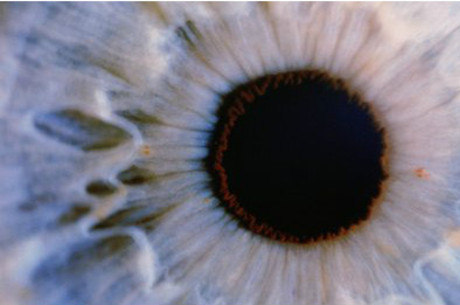

Os fotorreceptores são células da retina que detectam a luz e as convertem em sinais elétricos enviados ao cérebro.

Agora, experimentos realizados com ratos por uma equipe do Moorfields Eye Hospital e University College London, mostrou que o mau funcionamento desses fotorreceptores pode ser tratado com células-tronco.

Retina em laboratório

A equipe usou uma nova técnica que reconstruiu uma retina em laboratório, extraindo dela milhares de células-tronco que foram amadurecidas para serem transformadas em fotorreceptores e injetadas nos olhos de ratos cegos.

A pesquisa concluiu que essas células puderam se conectar com a arquitetura do olho e começar a funcionar.

No entanto, a eficiência das novas células ainda é baixa. Apenas mil de um total de 200 mil células transplantadas foram absorvidas de fato pelo olho.

O pesquisador-chefe, Robin Ali, disse à BBC que os resultados são prova de que os fotorreceptores podem ser transplantados de uma fonte de células-tronco embrionárias e abrem caminho para testes em humanos.

— Estamos tão animados. É possível dizer que cinco anos são um prazo realista para começar os teste clínicos.

O olho é um dos campos mais avançados em pesquisas usando células-tronco.

As células sensoras da luz precisam transmitir sinais elétricos para apenas mais uma célula antes que a mensagem chegue ao cérebro, ao passo que, no caso do tratamento da demência, as células devem se conectar com muitas outras em várias regiões do cérebro.

O sistema imunológico do olho é também muito fraco, diminuindo as chances de rejeição do transplante.

Além disso, poucas células já podem fazer a diferença. Dezenas de milhares de células-tronco são suficientes para melhorar a visão, enquanto que o mesmo número não seria capaz de regenerar órgãos maiores, como o fígado.

Chris Mason, do University College London, disse à BBC que a pesquisa é um grande avanço, mas a eficiência ainda é baixa para uso clínico. r7.com